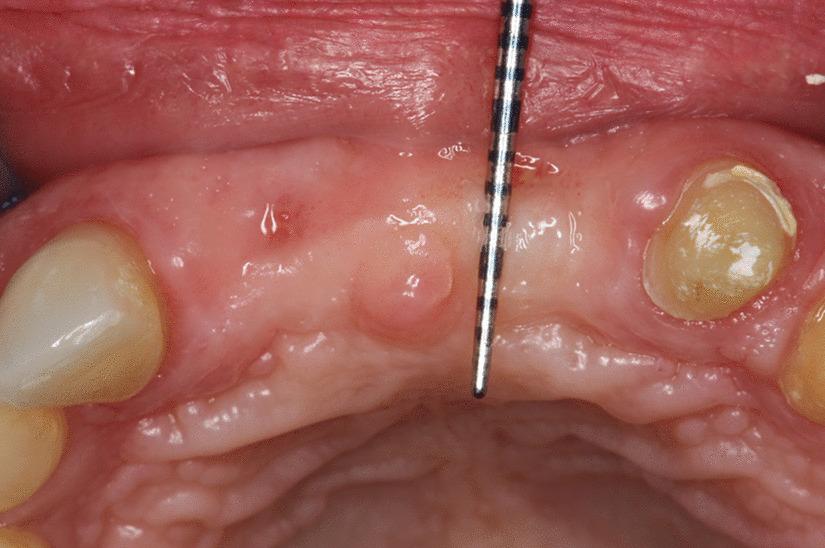

A total of 9 teeth were extracted from 5 patients. The extracted teeth were prepared immediately with the Bonmaker device. The extraction sockets were filled up with ATB powder. Six months after extraction, standardized intraoral x-rays and CBCT scans were performed. Re-entry was performed under local anaesthesia. Core biopsies were harvested for histological analysis and implants were placed.

从 5 名患者中总共拔出 9 颗牙齿。用 Bonmaker 设备立即对拔出的牙齿进行准备。用 ATB 粉末填充拔牙窝。拔牙后 6 个月,进行标准化的口腔内 X 光和 CBCT 扫描。在局部麻醉下进行再进入。采集核心活检进行组织学分析并植入种植体。